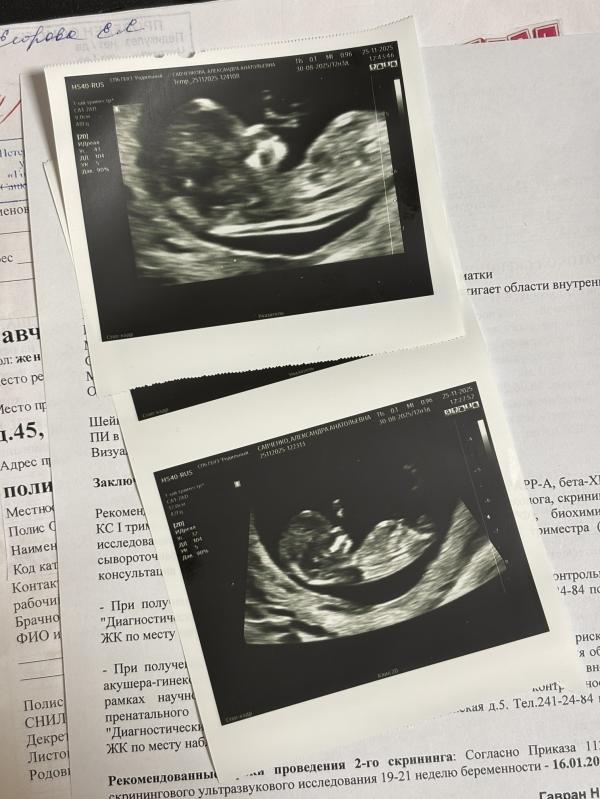

Вчера прошла первый скрининг в Родильном доме №6 им.проф. В.Ф. Снегирёва.

Просторный.Хорошая аппаратура.

Прямо перед моим лицом находился монитор (можно рукой потрогать.Настолько близко.)

Я видела все,что смотрела врач у себя на экране.

Врач озвучивала всё,срок почти сровнялся с месячными.(по ним было 12.3,я думала у меня 11.4,а оказалось 12.Какие-то показатели были на 12.3)

Сделала мне 3 фотографии крошки.

Фотографии не прибивали степлером к узи.Дали отдельно.

Врач смотрела бережно.Сначала через животик,потом трансвагинально.